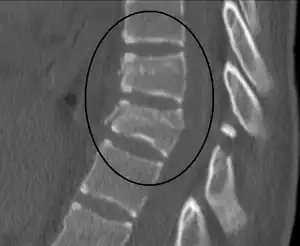

| A Chance fracture of T10 and fracture of T9 due to a lapbelt during an MVC. | |

Diagnosis is by medical imaging including CT scan.[9] It may be mistaken for a simple compression fracture.[5] Treatment may be conservative with the use of a brace or via surgery.[2]

A CT scan of the chest, abdomen, and pelvis is recommended as part of the diagnostic work-up to detect any potential abdominal injuries.[9][8] MRI may also be useful.[8] The fracture is often unstable.[1]